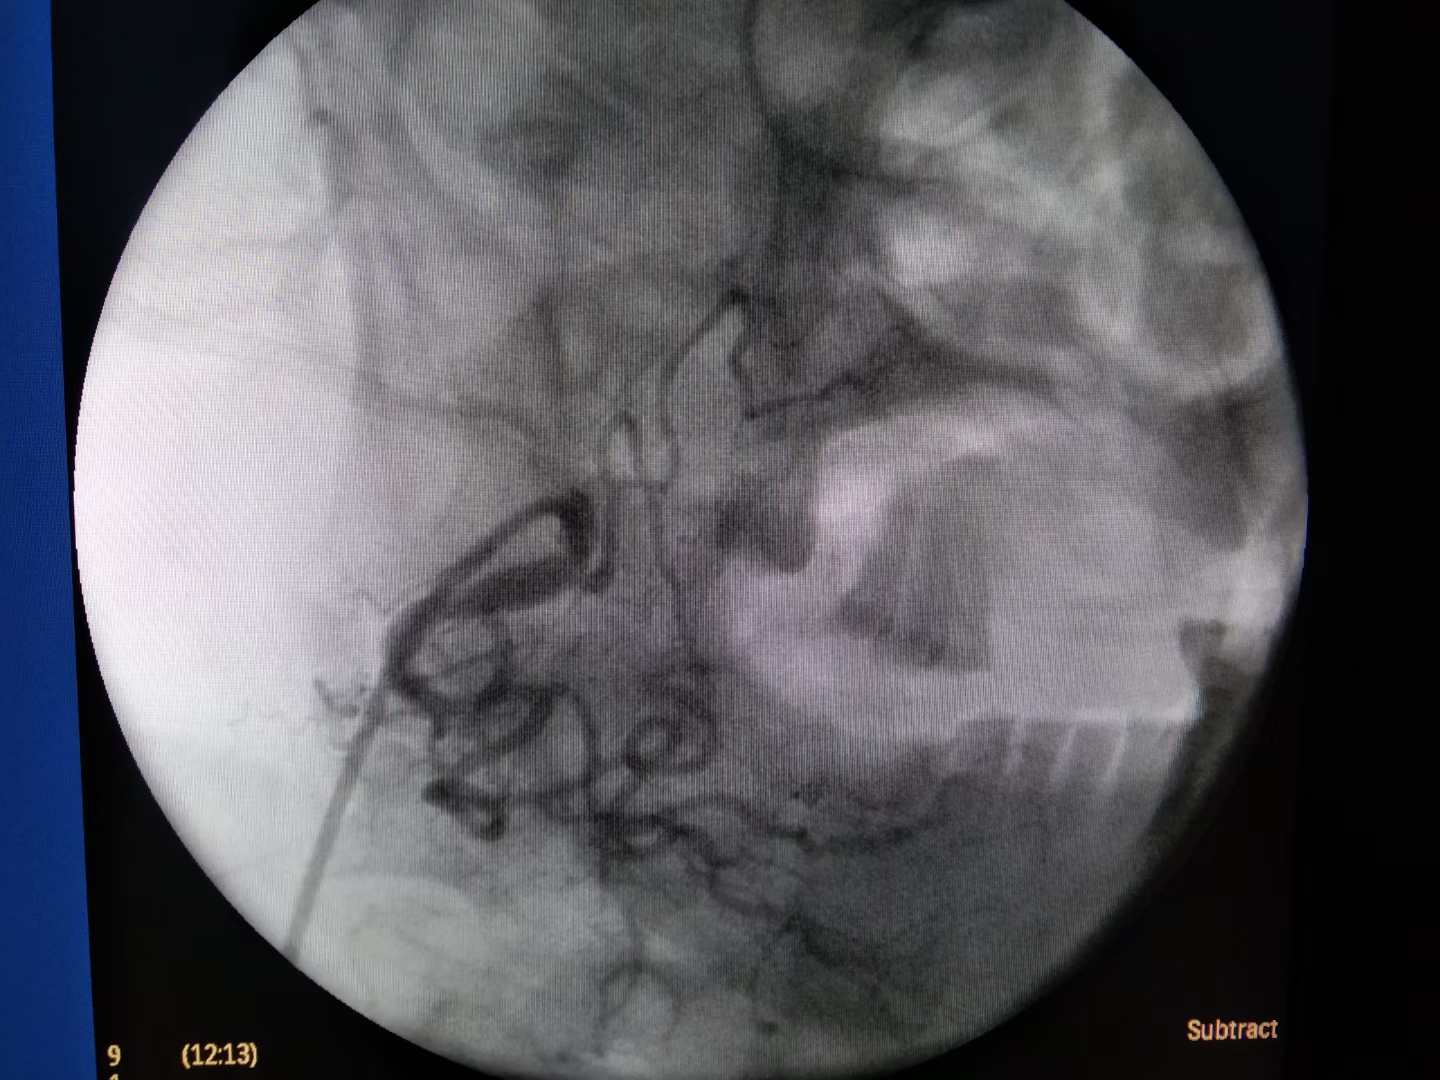

边扩容,输血,止血的同时,推入介入室。消毒、铺巾、穿刺、插管,造影。

最终,颗粒+弹簧圈完美栓塞。出血停止,患者生命体征平稳。